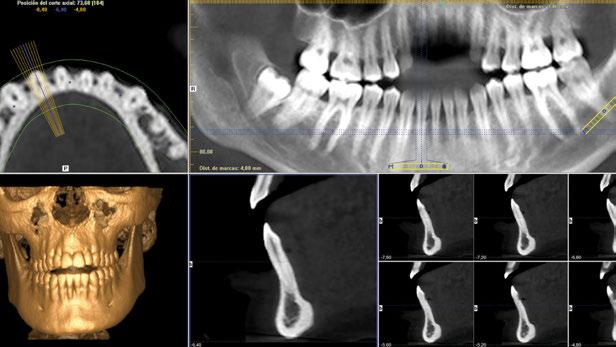

Figura 2. Radiografía tridimensional basal donde se aprecia la ausencia de tabla vestibular en el diente en posición de 41.

Figura 9. Radiografía tridimensional basal donde se aprecia la ausencia de tabla vestibular en el diente en posición de 31.